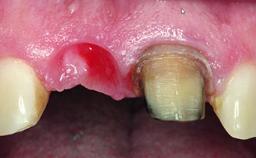

A healthy 28-year-old female patient presented for a consultation on treatment options to restore her upper right central incisor. At the clinical examination, the tooth responded to percussion and palpation. The gingiva was red and slightly swollen, with a mid-facial probing depth of 10 mm. The upper right lateral incisor showed no signs or symptoms, did not respond to exploration and percussion, and the vitality test was positive. The periapical radiograph revealed that tooth 11 had been endodontically treated, with no lesion evident at the apex. A small radiopaque calcified structure surrounded by a narrow radiolucent zone (3 × 3 mm) was present at the apex of tooth 12.

Bone Augmentation Horizontal|Simultaneous

Augmentation Materials Autogenous chips|Xenogenous|Membrane